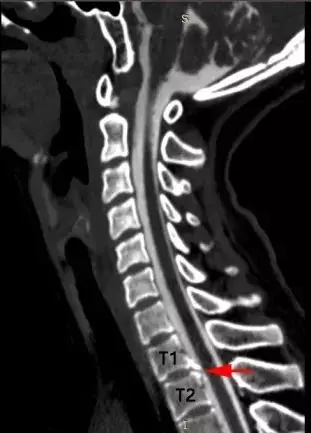

宋先生的脊柱磁共振檢查

可見第2、3胸椎之間有「骨刺」形成(紅箭頭)

刺破硬脊髓膜,造成腦脊液外漏(藍箭頭)

江女士的脊柱磁共振檢查

可見第1、2胸椎之間有「骨刺」形成(紅箭頭)

警惕腦脊液外漏、脊柱退變

此前,浙江大學醫學院附屬邵逸夫醫院神經內科曾接連接診了兩個年輕的「低頭族」,長時間低頭用電腦、玩手機 而頭痛難忍。經醫院檢查顯示,患者頸段椎間盤退變 ,形成骨刺並刺破了硬脊髓膜 ,造成了脊髓腦脊液滲漏 ,顱內壓力過低還造成了腦膜血管撕裂和硬膜下出血。